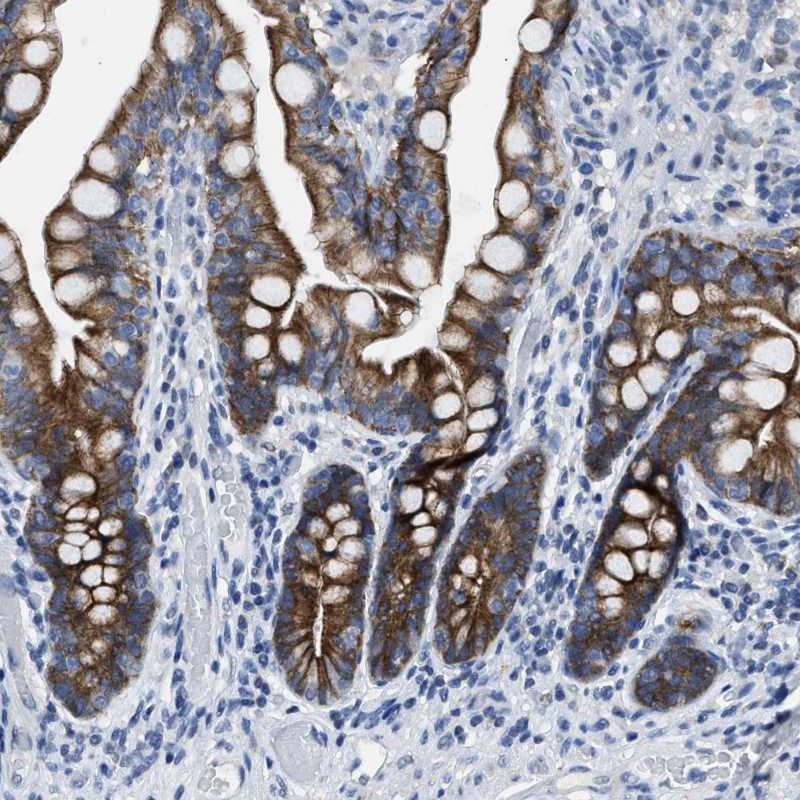

Immunohistochemical staining of human small intestine shows strong cytoplasmic positivity in glandular cells.